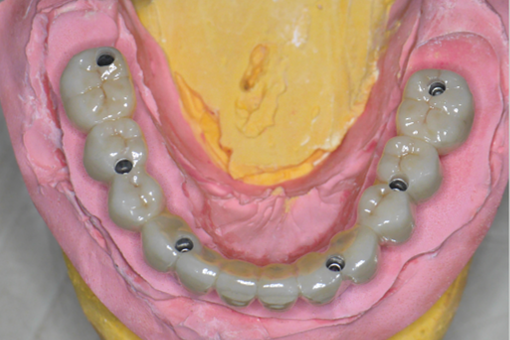

即刻安裝臨時固定假牙: 利用先進的CAD/CAM技術或預成連接件,在植體植入當天,立刻為張阿姨裝上一副堅固耐用的臨時固定假牙。這意味著張阿姨在離開診所時,嘴裡已經擁有了一副可以馬上使用的固定牙齒!

臨時固定假牙讓張阿姨舒適地度過了約3個月的骨整合期(人工牙根與骨頭緊密結合的關鍵時期)。3個月後,骨頭癒合穩固,張阿姨回診,醫療團隊為她取下臨時假牙,換上量身定制、更美觀、更堅固耐用的正式固定假牙。